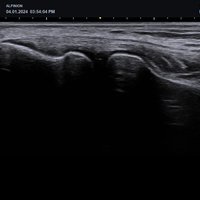

Mit dem X-CUBE 50 erweitert ALPINION seine X-CUBE Serie an hochmodernen Ultraschallgeräten. Das X-CUBE 50 bietet mithilfe der X + Architecture und einem besonders abgestimmten Sondenportfolio, zu dem auch Single Crystal Schallköpfe unserer High-End Systeme gehören, eine extrem wirtschaftliche Ultraschalllösung mit beeindruckender Bildqualität.

Dieses intelligente Ultraschallsystem, das auf automatisierten Tools und einem verbesserten Workflow basiert, ermöglicht den Verzicht häufiger Anpassungen durch den Arzt und erhöht so die Genauigkeit und Effizienz bei der Diagnostik. Mit seiner kompakten Bauweise ist das X-CUBE 50 auch in kleinen Behandlungszimmern einsetzbar.

X + Architecture

Die X + Architecture ist eine innovative Technologie, die von ALPINION entwickelt wurde, um die Leistung und Effizienz der Ultraschallsysteme zu verbessern. Durch die Integration fortschrittlicher Algorithmen und Hardwarekomponenten ermöglicht die X + Architecture eine schnellere Bildverarbeitung, höhere Bildqualität und eine präzisere Diagnose. Diese Technologie trägt dazu bei, die Genauigkeit und Zuverlässigkeit der Ultraschalluntersuchungen zu steigern und den Arbeitsablauf in medizinischen Einrichtungen zu optimieren.

X + Fit

Die ausgefeilte parallele Beamforming-Technologie X + Fit ermöglicht durch das Senden, Empfangen und Verarbeiten großer Datenmengen in hoher Geschwindigkeit eine Verbesserung von Kontrast und Gleichmäßigkeit für eine hervorragende Auflösung.

Durch den Einsatz der harmonischen Signalverarbeitungstechnik werden Signalverluste minimiert und die Bandbreite des vom Schallkopf übertragenen Signals verbessert. Dies führt zu einer Reduzierung von Artefakten und gleichzeitig werden Auflösung, Kontrast und SNR verbessert, so dass eine optimale Darstellung von Läsionen ermöglicht wird.

Full SRI TM – Speckle Reduction Imaging